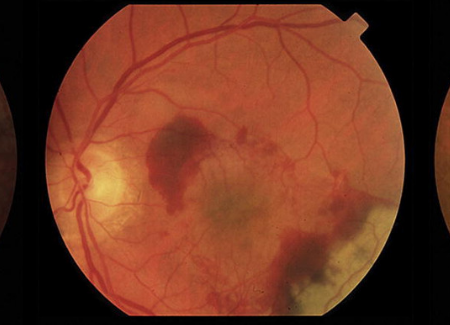

Age-Related Macular Degeneration (AMD)

The AMD Center of Excellence is dedicated to unraveling the complex and multifactorial causes of AMD, the leading cause of blindness in developed countries.